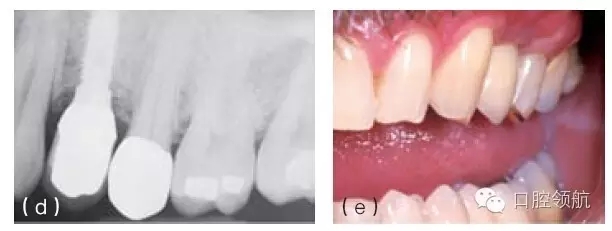

圖10.3 種植體位置靠遠(yuǎn)中,嘗試使用個性化基臺糾正植入位置的偏差。但是由于種植體位置過于靠遠(yuǎn)中,基臺的頸部位于鄰近磨牙鄰面接觸區(qū)以下。這個位置將阻礙修復(fù)體在基臺上就位,同時(shí)單冠的近中會出現(xiàn)懸突。需要取出種植體,并在缺牙區(qū)近遠(yuǎn)中向的中心區(qū)重新植入新的種植體。